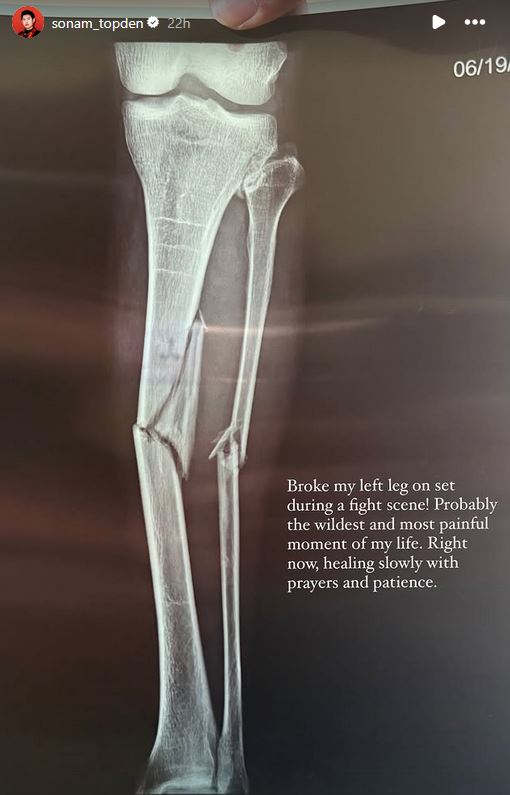

एक महिनादेखि बागलुङको ढोरपाटन क्षेत्रमा छायांकन भइरहेको फिल्म ‘ऐरी’मा लडाइँको दृश्य खिच्ने क्रममा अभिनेता सोनम तोप्देनको खुट्टा भाँचिएको छ । उनको बायाँ खुट्टा भाँचिएको हो । यसको जानकारी उनी स्वयंले सामाजिक सञ्जालमार्फत गराएका छन् । उनले खुट्टाको एक्स-रे तस्वीर फेसबुक स्टोरीमा सेयर गर्दै यो आफ्नो जीवनकै सबैभन्दा दर्दनाक क्षण रहेको बताएका छन् ।

सोनमले लेखेका छन्, ‘सेटमा एक लडाइँको दृश्यको क्रममा मेरो बायाँ खुट्टा भाँचिएको छ । सायद यो मेरो जीवनको सबैभन्दा भयानक र दर्दनाक क्षण हो । अहिले प्रार्थना र धैर्यका साथ विस्तारै ठीक हुँदैछु ।’ उनको एक सातादेखि पोखराको नागढुङ्गास्थित चरक मेमोरियल अस्पतालमा उपचार भइरहेको छ । हेलिकोप्टर चार्टर्ड गरेर उनलाई फिल्मको सेटबाट अस्पताल लगिएको थियो ।